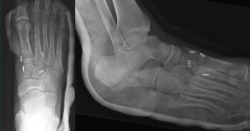

Figura 2. Caso 1. Resultados radiográficos posquirúrgicos.

Se realiza la intervención quirúrgica a las 8 semanas con reducción abierta mediante abordaje dorsomedial confirmando la inestabilidad articular y realizando una estabilización con sutura intraósea con botón de C1-M2. Se comprueba que aún persistía cierta inestabilidad en el plano frontal, por lo que se decide poner otro dispositivo de C2 a M1. Se inmoviliza con una férula suropédica y se indica descarga (Figura 2).

Figura 4. Caso 2. Radiografías lateral y anteroposterior sin carga de control tras la cirugía con fijación no rígida.

Se realiza cirugía con 2 suturas intraóseas C1-M2 y C2-M1 mediante la técnica descrita anteriormente (Figura 4). Se siguió un protocolo posquirúrgico igual al del caso anterior: revisión de la herida a los 10 días, descarga hasta las 6 semanas, carga parcial hasta las 8 semanas con bota y comenzar la carga completa con calzado cómodo con plantilla con soporte de arco longitudinal interno hasta un año postoperatorio.